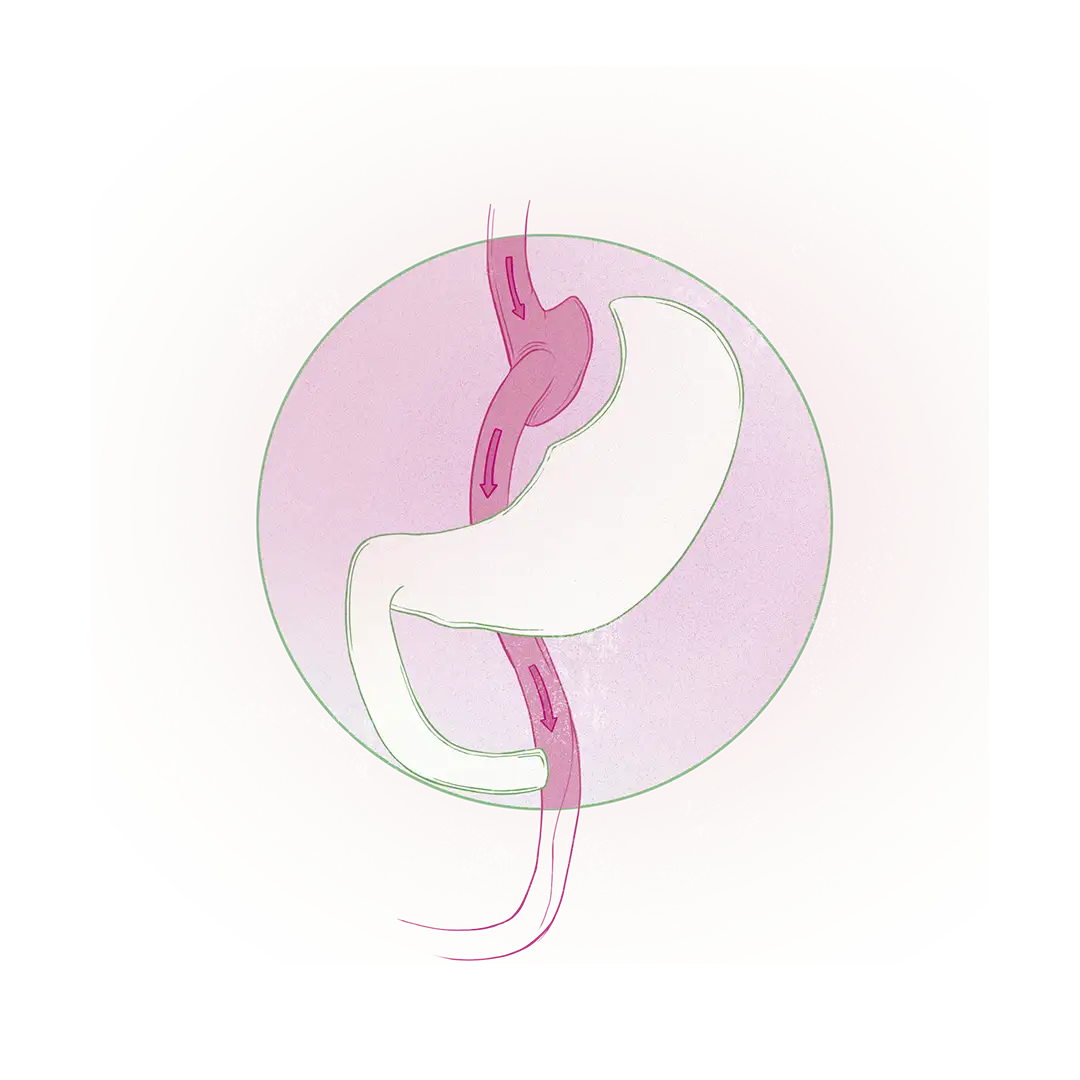

- Cirugía bariátrica restrictiva: Restringe los volúmenes de comida que el paciente puede ingerir al eliminar quirúrgicamente un 80% del estómago. En esa categoría hay una operación avalada que se conoce como manga gástrica.

El tipo de cirugía para cada paciente se escoge según la edad, la cronología de la obesidad, las enfermedades asociadas (como la diabetes o la hipertensión) y el grado de obesidad diagnosticado, que se basa en el índice de masa corporal (IMC). “Si la persona tiene menor grado de obesidad y pocas enfermedades asociadas, lo ideal será la manga gástrica; sin embargo, cada caso se evalúa individualmente", agrega Ospina.